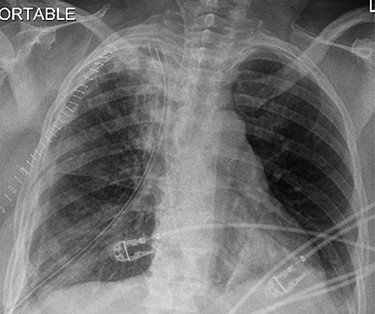

This is the case of a healthy 54-year-old female with a 3 month history of worsening dyspnea on exertion, nonproductive cough, general malaise and arthritic symptoms of her distal joints. Also, with an associated new onset, 6-month history of clubbing of her nails. She denied smoking history, weight loss, fever or chills. On examination she was found with clubbing of her nails (see Figs 1 and 2), and absent right thoracic breath sounds. Initial Chest X-ray (CXR) revealed a right side intrathoracic mass occupying the right thoracic cavity (see Fig. 3). She underwent a Chest computerized tomography (CT) scan with intravenous contrast revealing a large heterogenous mass 19 cm × 16 cm × 15 cm without gross calcifications (See Fig. 4). Then a CT-guided core needle biopsy was performed and was consistent with a benign SFT. In view of the mass size and worsening dyspnea, mass excision was performed by a single right side thoracotomy.

Initial CXR with compressed right lung, possible mass lesion and pleural effusion.